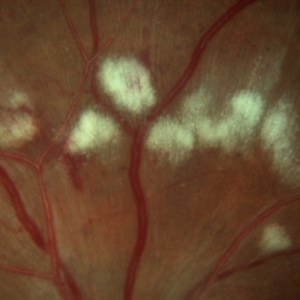

Cotton Wool Spots

Mar 1 2014 by Homayoun Tabandeh, MD, FASRS

Cotton wool spots in a patient with hypertension and diabetes

Condition/keywords: cotton wool spots, diabetic retinopathy, hypertensive retinopathy